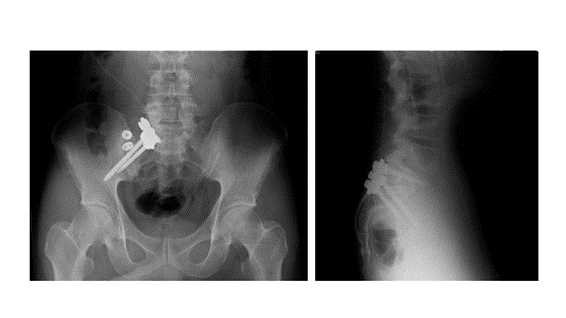

難治例には手術治療も

保存療法を6か月以上続けても荷重障害が残り、歩行や座位の持続が困難な重症例に対しては、仙腸関節固定術を行うこともあります。この手術は、荷重をしっかりと伝えられない状態を改善し、仙腸関節を安定させることを目的としています。当院では、1999年から前方固定術を行い良好な成績を得てきましたが、近年はより低侵襲な後方固定術を中心に実施しています。手術後は、痛みの改善とともに、座位や歩行時間の延長、日常生活動作(ADL)の向上が期待できます。